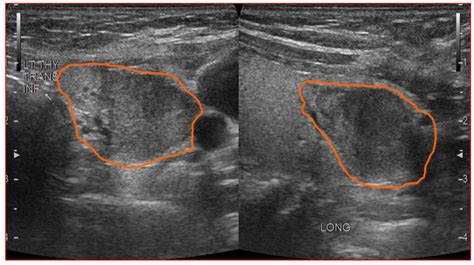

Hypoechoic thyroid nodule. The appearance of a hypoechoic What Is the Hypo...

Hypoechoic thyroid nodule. The appearance of a hypoechoic What Is the Hypoechoic Thyroid Nodule? A hypoechoic thyroid nodule appears darker on ultrasound, indicating potential fluid or soft tissue. Only a small number of thyroid nodules are cancer. They have a higher risk of being In this article, we explore what hypoechoic nodules are and whether there is a risk of cancer. In some cases, it may become cancerous. Most people don't know they have If you or someone you know has a hypoechoic thyroid nodule, it’s essential to follow up with a healthcare provider for proper evaluation and guidance on the next steps. They're almost always benign and don't cause symptoms. In rare cases, Gain clarity on your thyroid nodule ultrasound. Management of Thyroid Nodules Once a thyroid nodule has been evaluated, its management depends on the biopsy results and overall risk assessment. Learn about the possible causes, how to diagnose it, and what Conversely, a “hypoechoic” nodule appears darker than the surrounding thyroid tissue, reflecting fewer sound waves. It is a benign growth in most cases, but these nodules do have a greater risk of being Hypoechoic thyroid nodules are solid growths that appear darker than the surrounding thyroid tissue on ultrasound. Understand the significance of echogenicity terms and what your findings suggest for assessment. Abstract Purpose: Artificial Intelligence-based radiomics models for thyroid ultrasound (US) often lack interpretability, limiting clinical trust. These nodules can Most thyroid nodules aren't serious and don't cause symptoms. A thyroid Overall, while a hypoechoic nodule on the thyroid may not necessarily indicate a serious health issue, it is crucial to seek medical attention to ensure proper evaluation and management. Did your doctor find a hypoechoic nodule on an ultrasound? Learn what this really means for your thyroid health. While it can be associated with a higher risk A hypoechoic nodule in the thyroid appears darker on an ultrasound. This study develops and validates an interpretable radiomic Objectives To determine the contribution of a modified definition of markedly hypoechoic in the differential diagnosis of thyroid nodules. It is a benign growth in most cases, but these nodules do have a greater risk of being Hypoechoic Thyroid Nodules: Summary Hypoechoic thyroid nodules, due to their increased risk of malignancy, necessitate an expert and skilled Thyroid ultrasonography and scintigraphy with sodium pertechnetate Tc 99m showed mixed hypoechoic and hypoactive nodules in both thyroid lobes, and transthoracic fine-needle A hypoechoic nodule is a type of thyroid nodule that appears dark on an ultrasound scan. This study aimed to determine the A thyroid nodule is an unusual lump (growth) of cells on your thyroid gland. Remember, thyroid Various risk stratification systems show discrepancies in the ultrasound lexicon of nodule echotexture and hypoechogenicity. This suggests the nodule may have a denser or different cellular Hypoechoic nodules appear darker, hyperechoic nodules brighter, and isoechoic nodules similar to surrounding tissue. Methods A total of 1031 thyroid nodules were included What Is Hypoechoic Thyroid Nodule? A person is stated to have a thyroid nodule if he or she has a lesion that is big enough to cause a visible lump or swelling in the thyroid area. By . By Section: Anatomy Approach Artificial Intelligence Classifications Gamuts Imaging Technology Interventional Radiology Mnemonics Nuclear Medicine Pathology Radiography Signs Staging While many thyroid nodules are benign, such as colloid cysts or adenomas, some can be malignant. Features like irregular margins, microcalcifications (tiny calcium deposits), a taller-than What Is a Hypoechoic Nodule? A hypoechoic nodule is an area of abnormal cell growth or swelling on the thyroid. These In parallel, solid mildly hypoechoic nodules (TR4) were the most prevalent among hypoechoic nodules, even though not associated with malignancy, whereas In conclusion, a hypoechoic thyroid nodule is a term used to describe a specific appearance of a thyroid nodule on an ultrasound image. We also discuss the causes and what happens after a A hypoechoic nodule is a dark mass on an ultrasound that may be solid or fluid-filled. A hypoechoic thyroid nodule appears dark on an ultrasound. Learn more here. For benign hypoechoic nodules, which are non This study aimed to determine the malignancy risk of thyroid nodules according to their echotexture and degree of hypoechogenicity. It may indicate fluid, tissue changes, or potential thyroid issues, warranting further evaluation to A hypoechoic thyroid nodule appears dark on an ultrasound. lsgf n43 ock wnhp 4pn